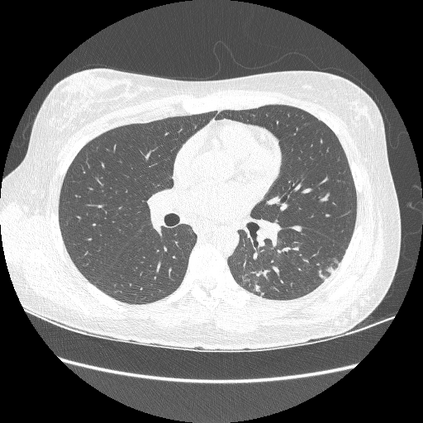

We propose a novel continual self-supervised learning (CSSL) framework for simultaneously learning diverse features from multi-window-obtained chest computed tomography (CT) images and ensuring data privacy. Achieving a robust and highly generalizable model in medical image diagnosis is challenging, mainly because of issues, such as the scarcity of large-scale, accurately annotated datasets and domain shifts inherent to dynamic healthcare environments. Specifically, in chest CT, these domain shifts often arise from differences in window settings, which are optimized for distinct clinical purposes. Previous CSSL frameworks often mitigated domain shift by reusing past data, a typically impractical approach owing to privacy constraints. Our approach addresses these challenges by effectively capturing the relationship between previously learned knowledge and new information across different training stages through continual pretraining on unlabeled images. Specifically, by incorporating a latent replay-based mechanism into CSSL, our method mitigates catastrophic forgetting due to domain shifts during continual pretraining while ensuring data privacy. Additionally, we introduce a feature distillation technique that integrates Wasserstein distance-based knowledge distillation (WKD) and batch-knowledge ensemble (BKE), enhancing the ability of the model to learn meaningful, domain-shift-robust representations. Finally, we validate our approach using chest CT images obtained across two different window settings, demonstrating superior performance compared with other approaches.